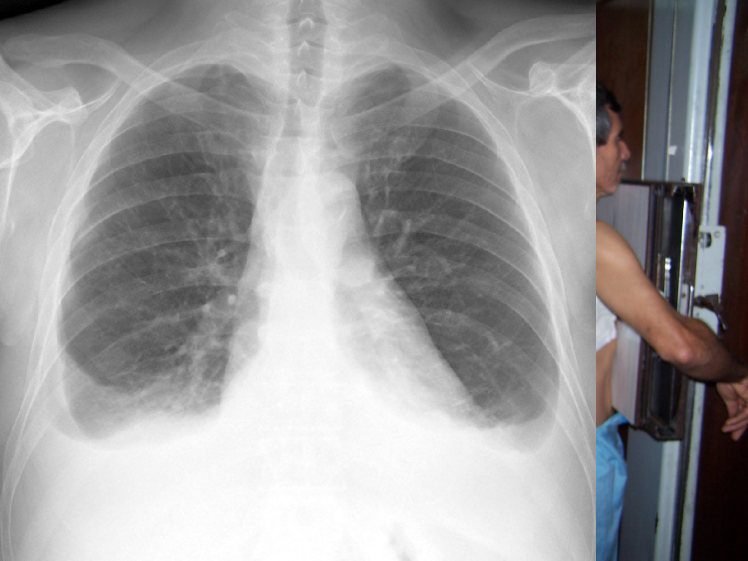

Figure 2: Common chest x-ray projections.

The projection information is highly relevant for diagnosis. For example, AP views, which are commonly used in pediatric patients, show an enlarged heart silhouette (Fig. 2(j)) that should not be interpreted as cardiomegaly, but merely the expected large-depth ratio of reversed organ observation (Fig. 3). Another illustrative example is the distinct pattern that pleural effusions have in the standing position (Fig. 4(a)), in which a typical meniscus sign is commonly found as opposed to decubit projections (Fig. 4(b)). Given that the number of different projections is unbalanced (for instance, PA followed by lateral projections typically comprise the majority of chest x-rays), there is the risk that none of the other projections will have sufficient instances with which to train models capable of discriminating pathological from non-pathological patterns in the context of the projection.

There are particular radiological landmarks that differentiate projections, which radiologists are trained to identify. For instance, in the case of PA projections, these landmarks are the presence of air in the gastric chamber and the scapulae projected outside the lung fields. Although these features can be learned, models trained in unbalanced datasets with a poor representation for different projections may not have sufficient instances to properly learn those patterns. An illustrative example is when the heart enlargement in AP projections is attributable only to the effect of the projection, while the trained model erroneously predicts cardiomegaly.